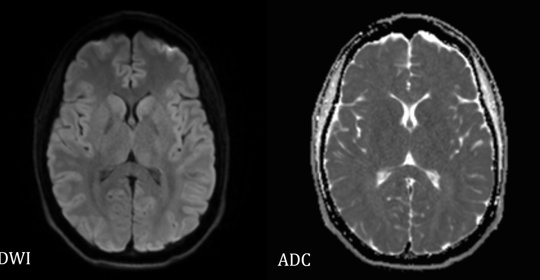

腦幹梗塞:前兆、原因、後遺症及治療方法

腦幹梗塞:診斷與治療

腔隙性腦梗塞:症狀、診斷與治療

腦幹梗塞:原因、症狀及治療方法

腦幹梗塞:症狀、恢復及預防